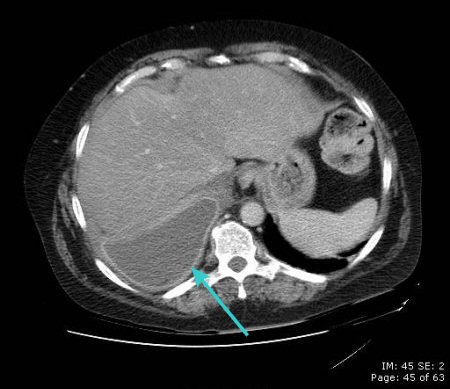

[Figure caption and citation for the preceding image starts]: CT scan of chest showing empyema necessitans (long arrow), a chronic untreated empyema that has eroded through the thoracic cage and formed a subcutaneous abscess (short arrow)From the collection of Dr Ami Rubinowitz; used with permission [Citation ends].